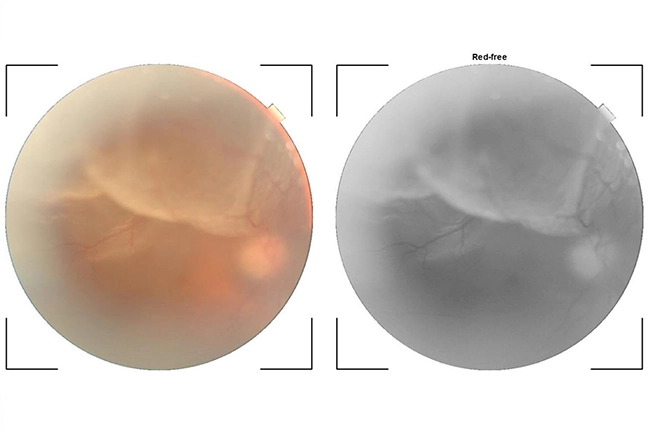

BRVO (branch retinal vein occlusion)

In BRVO, one of the main veins of the retina gets blocked. This leads to bleeding in the retina and swelling of the macula of the retina and results in decrease in vision. It is usually caused due to increased blood pressure with / without diabetes. It can be confirmed by OCT scan and effectively managed by intravitreal injections, laser and surgery.

CRVO (central retinal vein occlusion)

When all the veins of the retina get blocked, it is called as CRVO. Loss of vision occurs due to bleeding in the whole of the retina and severe swelling of the retina. It occurs due to increased blood pressure with / without diabetes. It is commonly treated by intravitreal injections and sometimes requires laser and surgery.